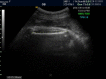

Background: Abdominal circumference (AC), biparietal diameters (BPD) and femoral length (FL) are now the main parameters used to obtain estimated fetal weight (EFW). Although the role of soft tissue parameters in determining fetal weight was proved but clinical attention to mid-thigh soft tissue thickness (STT) is limited.

Materials and methods: One hundred and fourteen normal singleton term (36-42w) pregnancies with delivery within 72 hours were randomly selected to participate in this prospective cohort study. Variables measured by ultrasonography before birth included: AC, BPD, FL and STT. The actual neonatal BW was also measured after birth. Linear regression model was used and R square and p-value were reported.

Results: The mean (SD) of BW was 3406 (405) gr. R square was best fit for the model that STT was added to AC, BPD, FL (r(2): 0.77). R square for the model using BPD, AC, FL and model using BPD, STT, FL was the same (r(2): 0.7). Best fit formula was Log (BW)= 2.461+0.003BPD+0.001AC+0.007STT+0.005FL.

Ac (r: 0.67, p<0.001), STT (R: 0.50, p<0.001), BPD (R: 0.59, p<0.001), FL (R: 0.66, p<0.001) were significantly correlated with birth weight. AC had also significant correlation with STT (p=0.001) CONCLUSION: This study showed adding STT to other variables in predictive models of fetal weight would provide a nice estimation (r(2)=0.77) and in cases that measuring AC is suboptimal STT may be a good replacement.